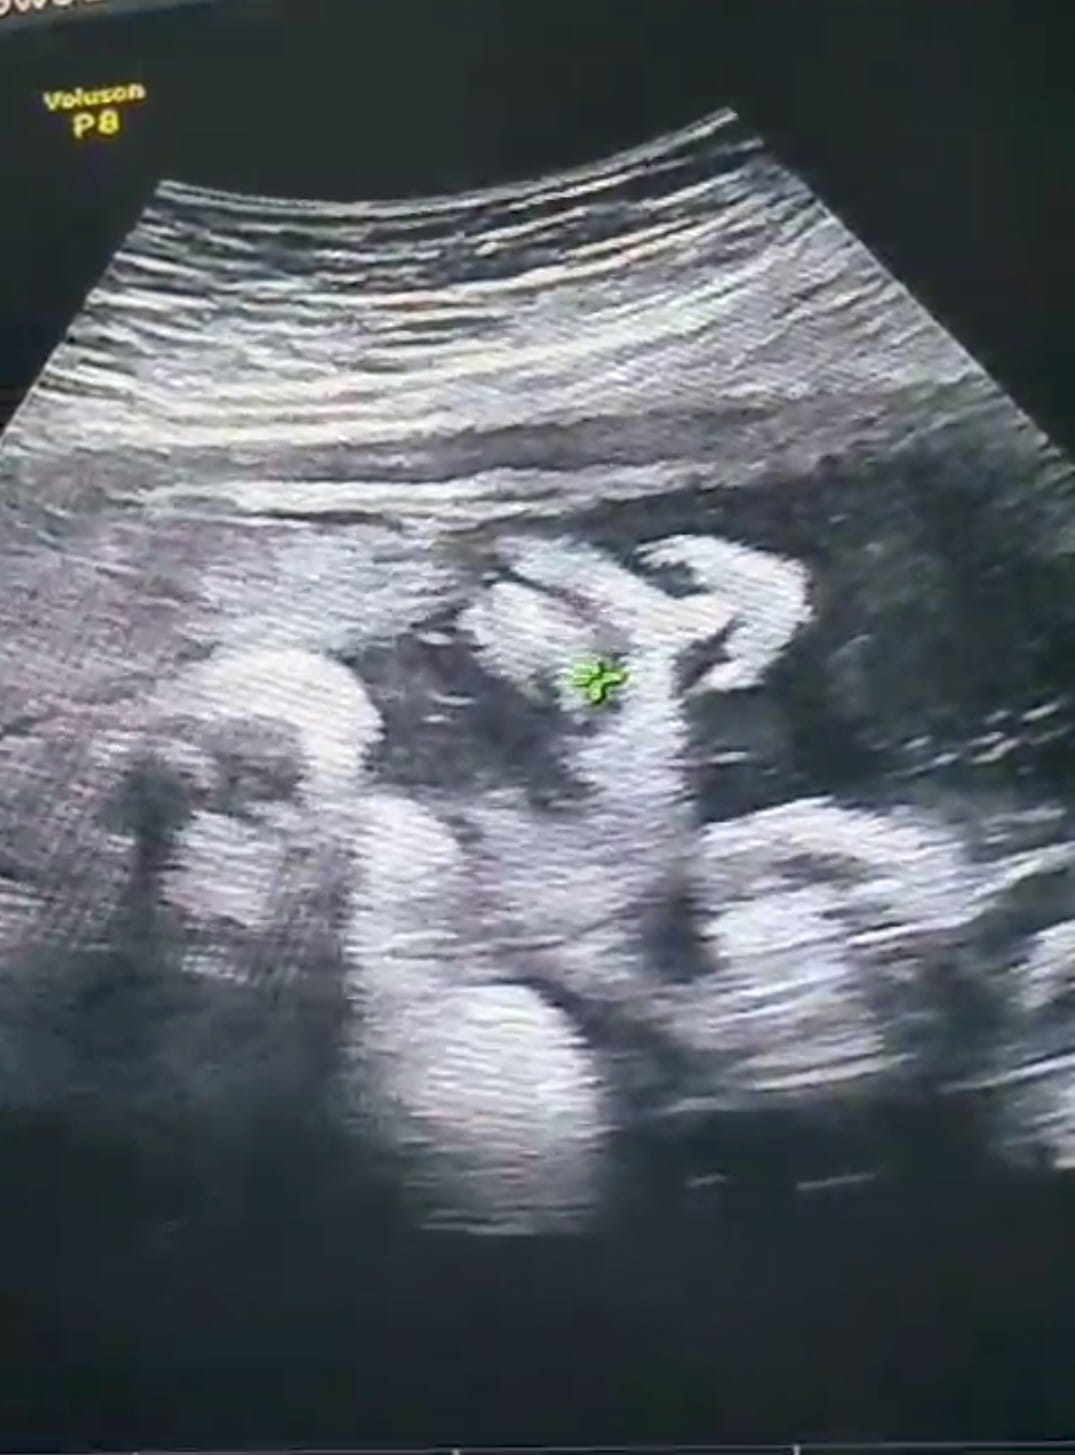

una eco y la nariz del padre